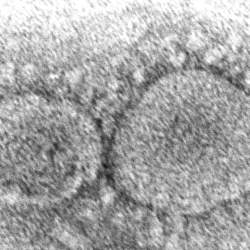

U.S. intelligence agencies are divided over whether a lab leak or a spillover from animals is the likely source of the deadly virus. -

Did COVID-19 originate in animals or leak from a Chinese lab? -